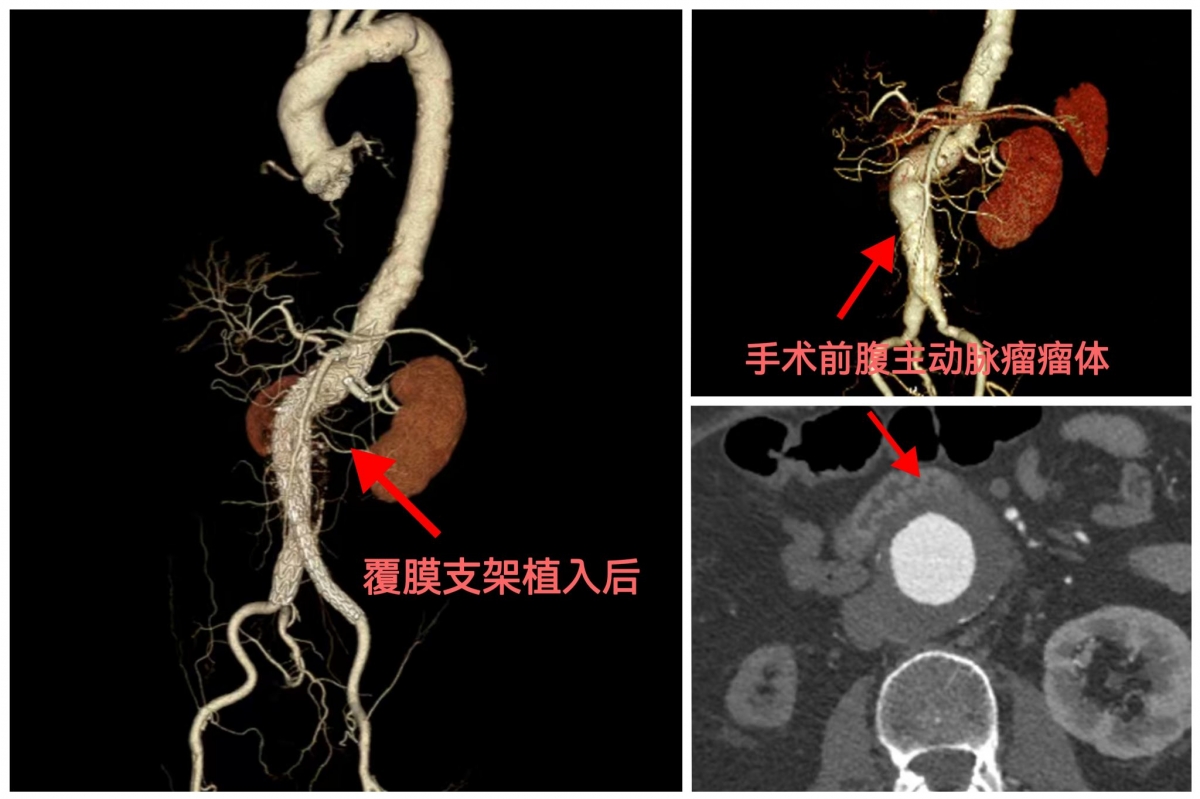

近日,广西壮族自治区南溪山医院血管外科成功完成了一例直径达 5.7cm、紧邻多脏器血管分支的腹主动脉瘤腔内覆膜支架隔绝手术。患者术后1个月复查时各项指标稳定,彻底卸下了压在心头多年的“大石头”。这标志着医院血管外科在复杂腹主动脉瘤的个体化治疗上迈出了关键一步。

70多岁的陈先生,多年前就被查出腹主动脉瘤,当时瘤体直径仅 3.9cm,可随着时间推移,瘤体不断增大至5.7cm—— 这一尺寸已远超“直径≥5cm需紧急干预”的医学标准,随时可能破裂引发大出血,堪称体内的“定时炸弹”。更棘手的是,陈先生的动脉瘤位置极为特殊:紧紧毗邻腹腔干、肠系膜上动脉、双侧肾动脉及左副肾动脉等重要血管分支。这些血管是肝脏、肠道、肾脏等关键脏器的“供血生命线”,一旦手术中损伤或阻断,极可能导致脏器缺血坏死。同时,陈先生还患有高血压和慢性肾功能不全,本身身体耐受度差。“高龄 + 大瘤体 + 高危位置 + 基础病”的四重风险叠加,让常规手术方案难以适用,也让手术风险陡增。

“体外开窗” 的核心,是为陈先生量身定制支架:手术前,团队在体外对支架进行精准测量和切割,在对应肠系膜上动脉、肾动脉等分支血管的位置 “雕琢” 出大小、位置完全匹配的 “窗口”;手术中,在先进 DSA 影像设备的实时引导下,团队通过微创切口,将这8枚支架依次精准植入血管内。整个操作如同 “在血管里搭积木”:主支架的 “窗口” 与脏器分支血管精准对接,辅助支架则进一步加固通路、隔绝动脉瘤腔。8 枚支架协同作用,既成功将动脉瘤与正常血管 “隔绝”,杜绝了破裂风险,又完整保留了所有重要脏器的血液供应,从根本上避免了肾功能进一步衰竭的可能。团队创新采用 “体外开窗” 技术个性化改装支架,一次性植入8枚支架为老人重建血管通路,不仅隔绝了动脉瘤风险,更保住了关键脏器血供。

陈先生术后恢复十分顺利,得益于团队精湛的技术和术后精心的护理,没有出现感染、支架内漏等任何并发症。术后 1 个月返院复查时,影像学检查显示:8 枚支架位置全部精准,支架内血流通畅,动脉瘤未再显影;肾功能、血压等关键指标也保持稳定。